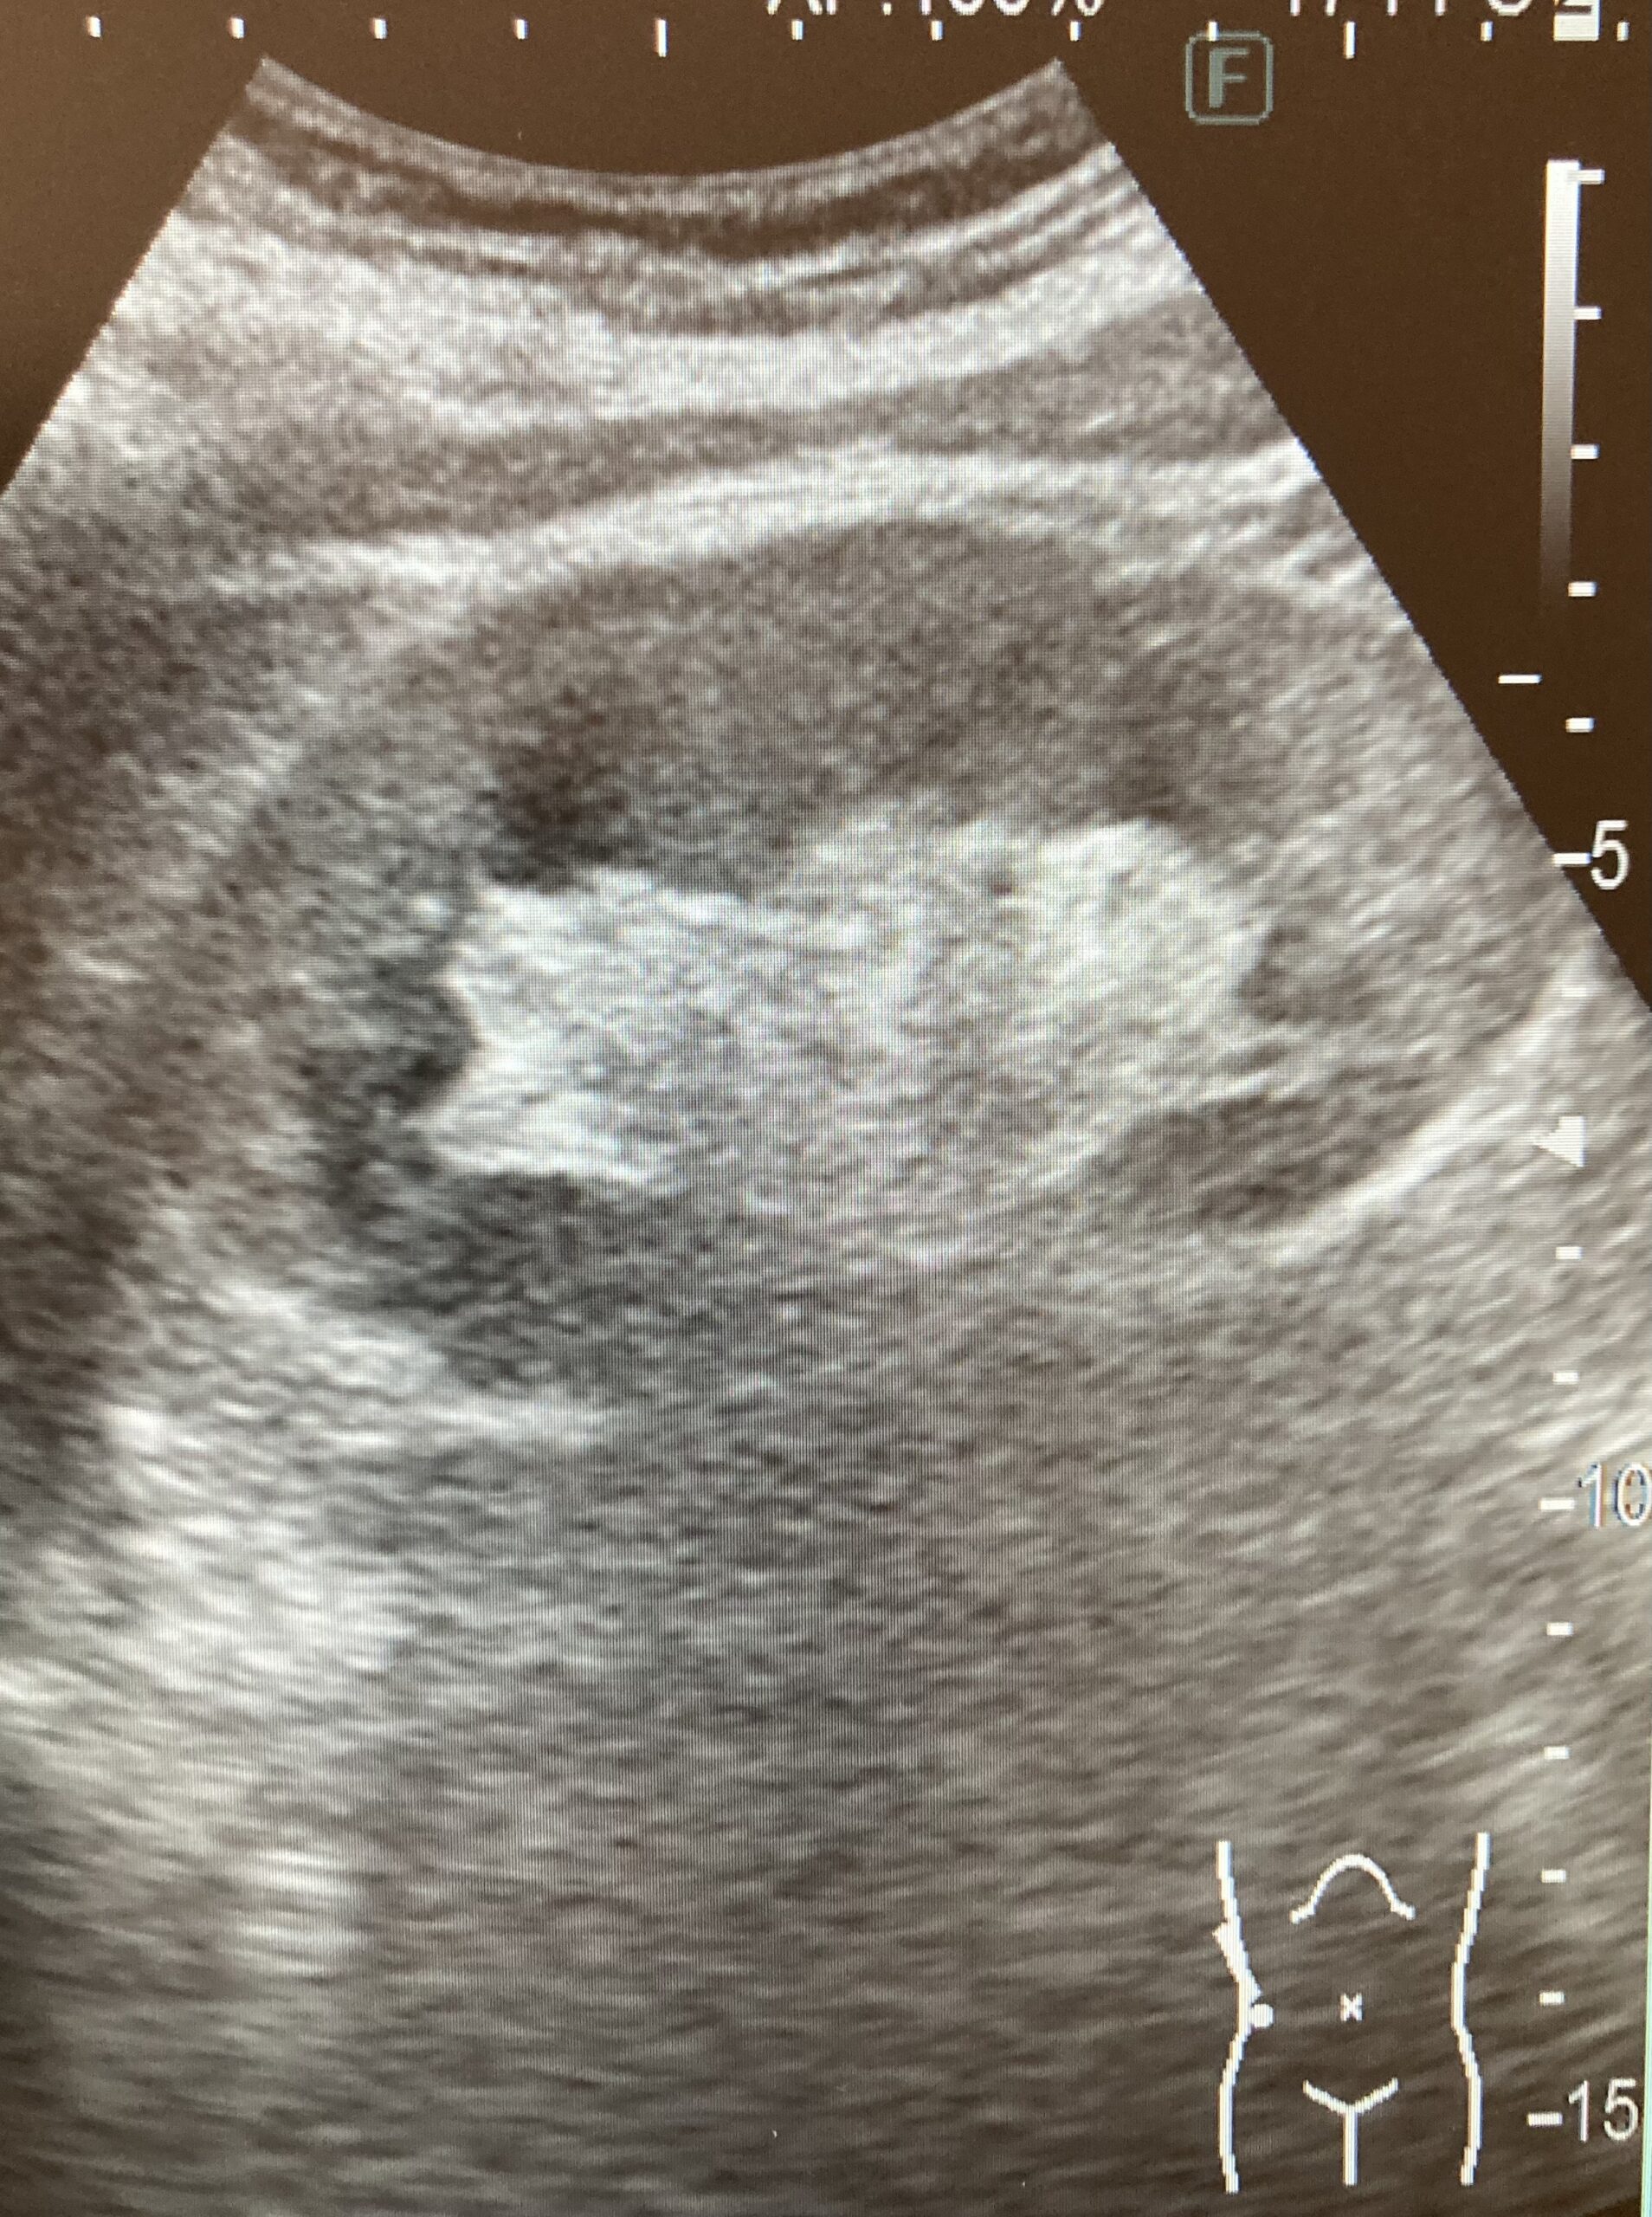

はじめてのエコー検査、どんなことをするの?検査技師がおこたえします♪

今日は、高山泌尿器科五条クリニックの検査技師から、【エコー検査(超音波検査)】についてお話します

当院では、大人からお子さんまで、症状に応じて幅広くエコー検査を受けていただいています。

エコー検査は、体の状態を画像で詳しく知ることができる、とてもたいせつな検査です。痛みはなく、おなかに機械を当てて、症状の原因となる所見がないかを探っていきます

特に、

頻尿、尿の出が悪い、尿に血が混じるなどの症状がある方、尿検査で異常を指摘された方に受けていただくことが多いですが、がんなど無症状のまま進行する病気もありますので、定期的な検査が大切です。

エコー検査では、残尿の量や、前立腺の大きさ、尿路に腫瘍や結石がないかどうかなどを見ていきます。

👆腎臓

👆前立腺と膀胱